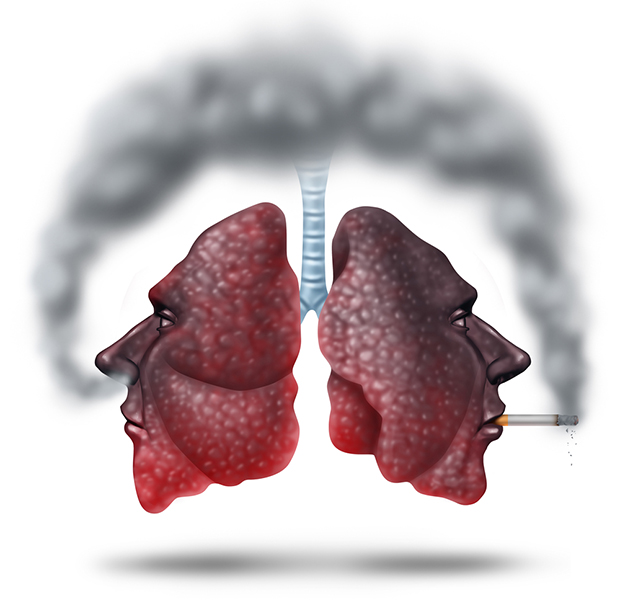

Здоровый образ жизни: Влияние курения

Раздел: Моменты озарения